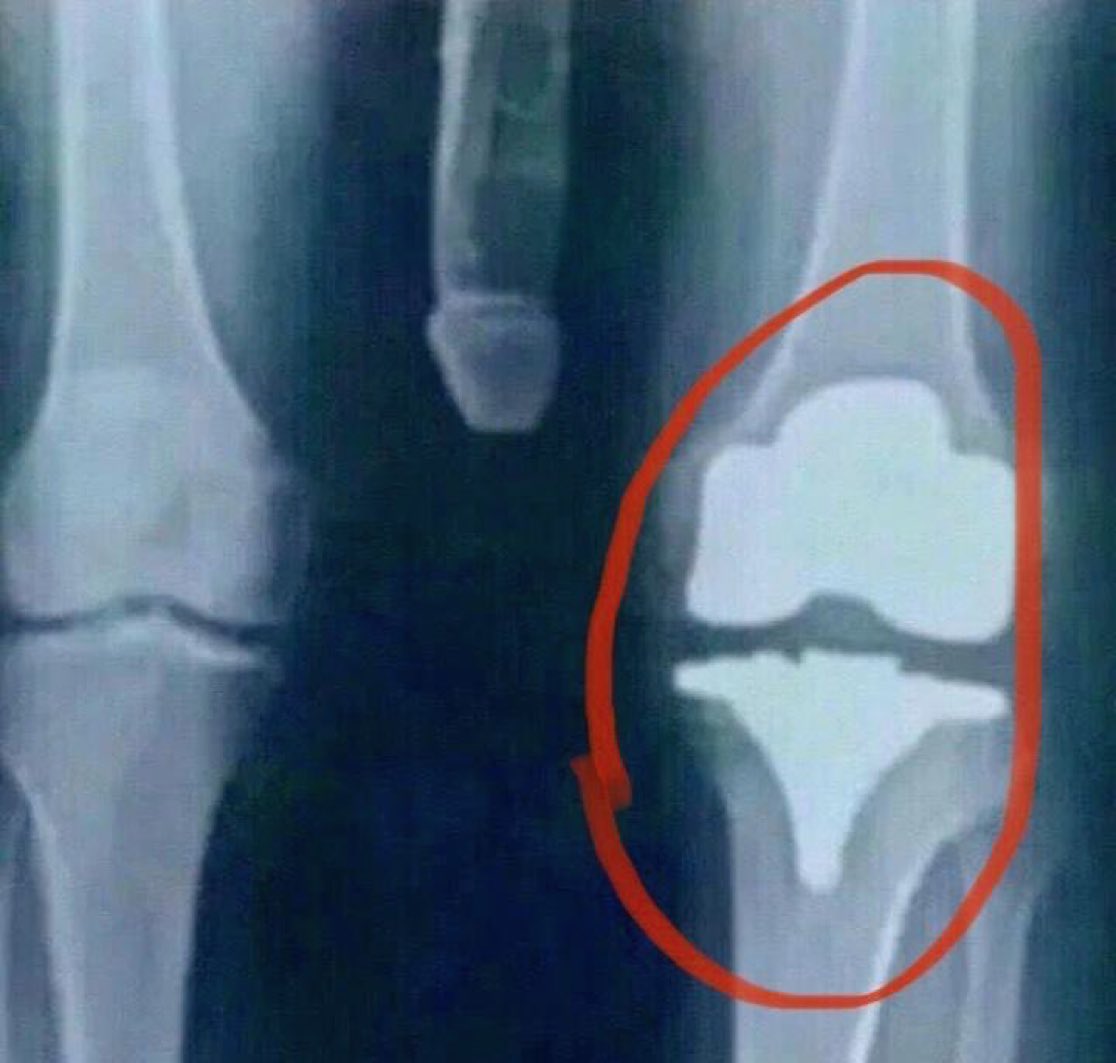

I’m bionic for real now 🦾